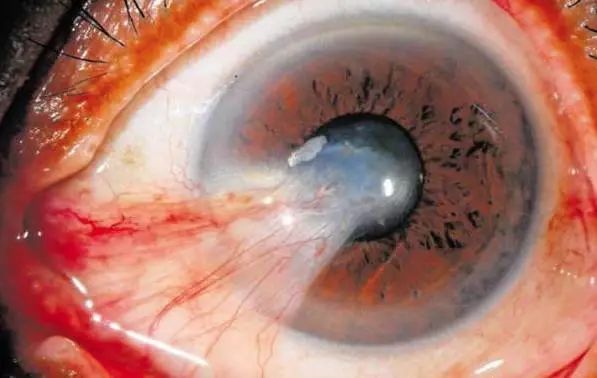

2.当胬肉头部抵达并逐步侵入角膜后,胬肉可(kě)以侵及角膜前弹力层及实质浅层,引起细胞浸润,导致胬肉头部附近角膜混浊。肥大而充血的胬肉可(kě)以压迫局部角膜引起散光,导致视物(wù)重影。可(kě)以手术。

3.当胬肉进展到瞳孔區(qū),不透明的胬肉组织遮挡瞳孔區(qū)光線(xiàn),会影响视力。这时,医生一般建议要做手术了。

4.若胬肉完全覆盖瞳孔區(qū),视力可(kě)下降至盲。并且因為(wèi)胬肉术后角膜会有(yǒu)疤痕生成,所以完全覆盖瞳孔的胬肉即使切除后,视力提高也有(yǒu)限。